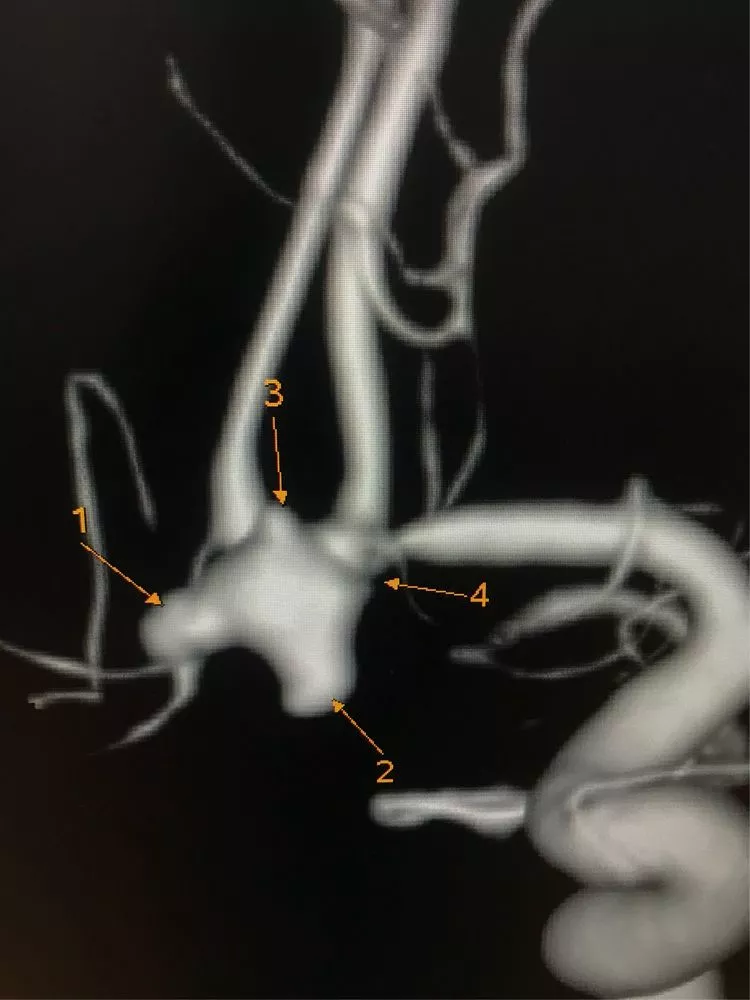

患者,女,46岁,头痛入院,头CT未见异常,行腰穿明确为蛛网膜下腔出血,DSA诊断为左侧前交通动脉瘤。

1、动脉瘤形态不规则,有二个大的子瘤。

2、血管痉挛明显,左侧A1远端及双侧A2近端均明显变细。

3、宽颈,同时对侧A1缺如,前交通动脉必须保持通畅。